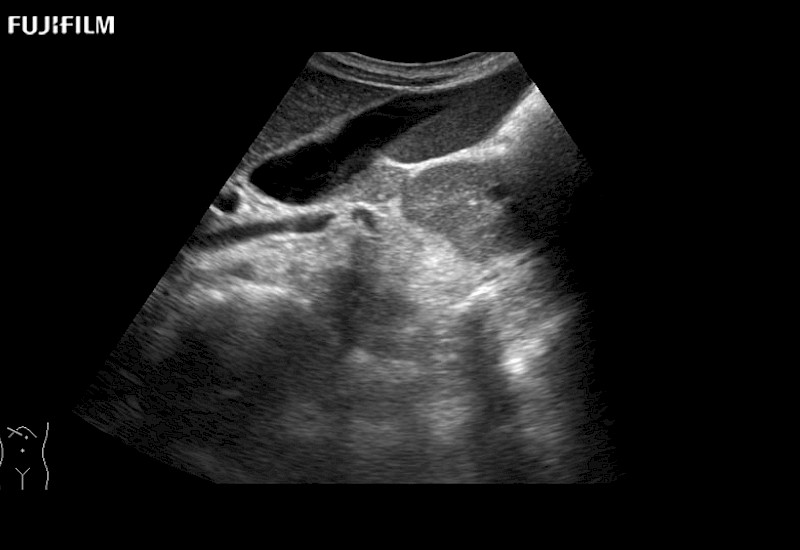

Extraordinary high-resolution digital imaging

for use during open and laparoscopic procedures: Tumor localization & staging, Ablation, Resection, Biopsy, Transplant, Abdominal exploration, Robotic surgery

- Exceptional near and far-field resolution

- Instant feedback on tumor margin delineation

- Valuable information to guide tumor resections

C9150LA - 4-way Laparoscopic Transducer

Curved array 4-way laparoscopic transducer for better visualization of targeted lesions.

- Built to withstand the rigors of daily laparoscopic surgery

- Ideal for liver and kidney scanning

- Exceptional near and far-field resolution

- Instant feedback on tumor margin delineation

L44LA - 4-way Laparoscopic Transducer

Exclusive linear array 4-way laparoscopic transducer for better visualization of targeted lesions.

- Built to withstand the rigors of daily laparoscopic surgery

- Ideal for liver and kidney scanning

- Exceptional near and far-field resolution

- Instant feedback on tumor margin delineation

UST-5550-R - Robotic Transducer

Exclusive linear array robotic surgery transducer.

- Provides complete surgeon control during robot-assisted procedures

- Ideal for liver and kidney scanning

- Exceptional near and far field resolution

- Instant feedback on tumor margin delineation